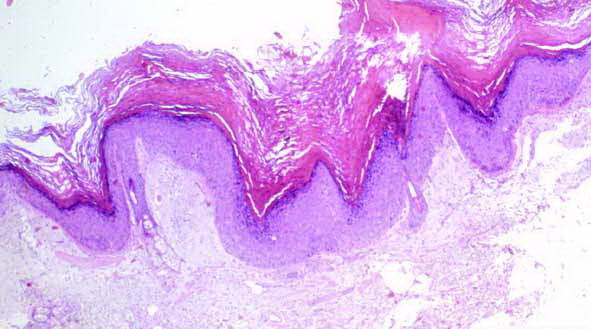

Verruca vulgaris = الثؤلول الشائع